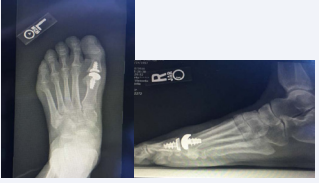

There were 14 patients involved, (eight females and 6 males), in this study. Of the 14 patients, this was a secondary procedure for four of them. Three patients had bilateral implants placed, while 11 patients had a single implant placed for a total of 17 implants. The average age of the patient was 60.8 years with the range being from 54-69, and the median age being 61 years old. Radiographs were taken pre and post operatively to assess each patient’s affected joint. Following surgical intervention, the patient’s progress was reassessed in the clinic at each postoperative appointment. The postoperative appointments were scheduled for 1 week, 2 weeks, 6 weeks, 3 months, and 6 months (Figure 14).

Figure 14: Checking proper implant placement and range of motion via intraoperative flouroscopy after insertion of the Arthrosurface total toe implant

The patient’s were then categorized into two groups: primary procedures and secondary procedures. A person undergoing a primary procedure meant that this was their first surgical intervention for addressing their hallux rigidus. A person in the secondary group meant that they had previous surgical intervention. A scoring system similar to that of the AOFAS scoring system was used, but tailored to the first metatarsal phalangeal joint. The three main categories of the scoring system were pain, function, and alignment. The higher the patient’s score total, the better the outcome of the procedure (Figure 15).